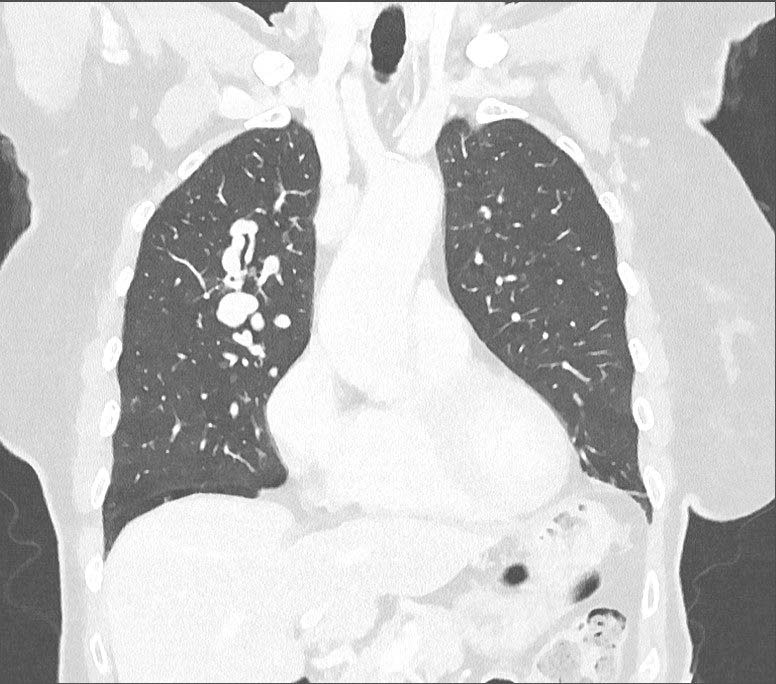

Een verrassende oorzaak van dyspneu: Rendu-Osler-Weber

Er komt een patiënte op het spreekuur die last heeft van inspanningsdyspneu en pijn op de borst. De huisarts denkt aan een cardiale oorzaak. Toch is er iets anders aan de hand, want er zijn klinische aanwijzingen voor een zeldzame aandoening: de ziekte van Rendu-Osler-Weber. Waar moet u op letten?